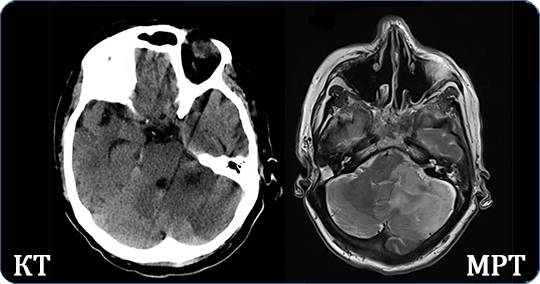

Несмотря на общую схожесть процедур, разница между МРТ и КТ все же есть. Принципиально разные цели исследования и задачи диагностирования. Сложно сказать, что из них информативнее, так как области обследования значительно отличаются.

При МРТ печени можно увидеть нарушения кровотока, наличие опухолей в тканях, при КТ позвоночника легко определить структурные изменения в костной системе, защемления суставов и артерий. МРТ органов малого таза выявит причину кровотечений, нервные защемления, воспалительные процессы в сосудах. КТ легких укажет на опухоли, отобразит структуру и позволит определить природу затемнений.

Иногда наиточнейшую информацию не удается получить после одной процедуры, и назначают тут же следующее исследование. Отличие диагностики КТ от МРТ позволяет методам друг друга дополнять и получать еще более полную картину состояния организма.

Компьютерная томография чаще всего назначается тем пациентам, у которых есть подозрения на аномалии развития костной системы, при поражении суставов, при неуточненных диагнозах, после получения травм или ушибов. КТ сможет отобразить состояние грыжи, легко установит отклонения в развитии суставов, поражения позвоночника и его отделов, покажет повреждения головного мозга, определит и уточнит природу заболевания органов грудной клетки, выявит болезни щитовидки, обнаружит камни или воспалительные процессы.

МРТ печени покажет разницу состояния мягких тканей, состояние сосудов и суставов. Обнаружит опухоли и новообразования в мягких тканях, отобразит избыточное внутричерепное давление, кровотечение. МРТ хорошо и подробно поможет изучить подкорковую область головного мозга, оболочки и структуры спинного мозга, поможет установить точный диагноз пациентам с неврологическими заболеваниями. МРТ печени и желудка установит проблемы желудочно-кишечного тракта, диагностирует тех, кто перенес инсульт или страдает судорожными симптомами, эпилепсией и другими нервными заболеваниями.

Томография головного мозга

Если в качестве ключевого критерия выбора выступает уровень информативности, то магнитная томографии окажется предпочтительней, поскольку обеспечит детализированный результат.

Даже КТ не может сравниться с магнитной томографией в информативности при обследовании мягких тканей и сосудистой системы.